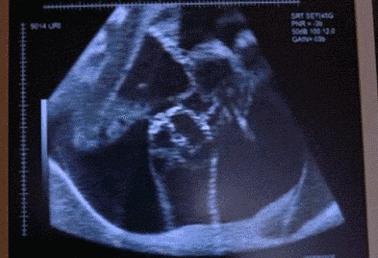

这位孕妈觉得去医院检查胎动很麻烦,就在网上买了超声胎心仪,自己在家听胎动。宝宝38周时,孕妈觉得胎动有些频繁,可用胎心仪检查,显示胎心在110--160次/分的正常范围内,想着可能是宝宝即将诞生,就没当回事。又拖了几天,感觉胎动越来越弱,才慌忙到医院检查。可专家一听,胎心压根就听不到了,原来胎儿在妈妈肚子里脐带绕颈五圈,因为没及时发现,宝宝缺氧很久,已经窒息了。

孕晚期胎动频繁是怎么回事呢?事实上,在第18周时,胎动开始出现(早的话,第16周就开始)。随着孕周的增加,胎动也逐渐增多,并且在第32周—34周达到高峰,在38周后会逐渐减少。这期间,胎动大于等于30次/12小时或大于等于4次/小时也为正常。但是,如果胎动少于20次/12小时或者3次/小时,孕妈妈们就要引起重视了。